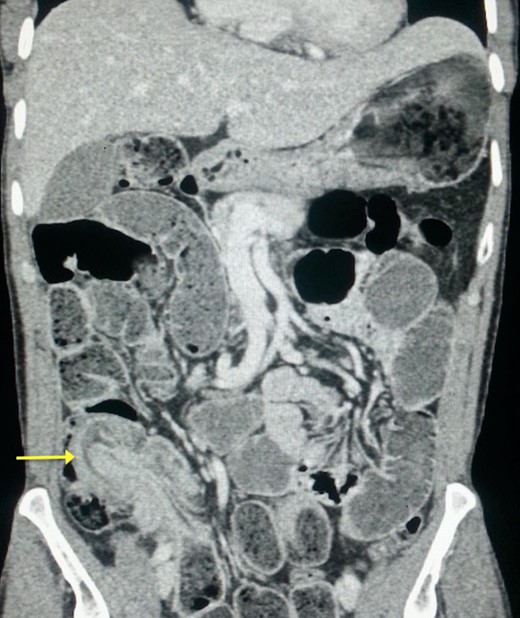

The post-operative outcomes were favorable. The pathological examination of the surgical specimen found an adenomatous ileal polyp with a high grade dysplasia on the terminal ileum being the cause of the ileocecal intussusception (Fig. 4).